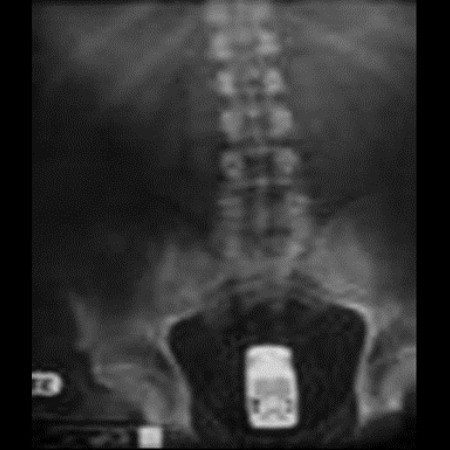

Çoğunun mazereti 'Yanlışlıkla üzerine düştüm'. İnsanların bağırsaklarında bulunan en ilginç cisimler sizi şok edecek.

Bardak